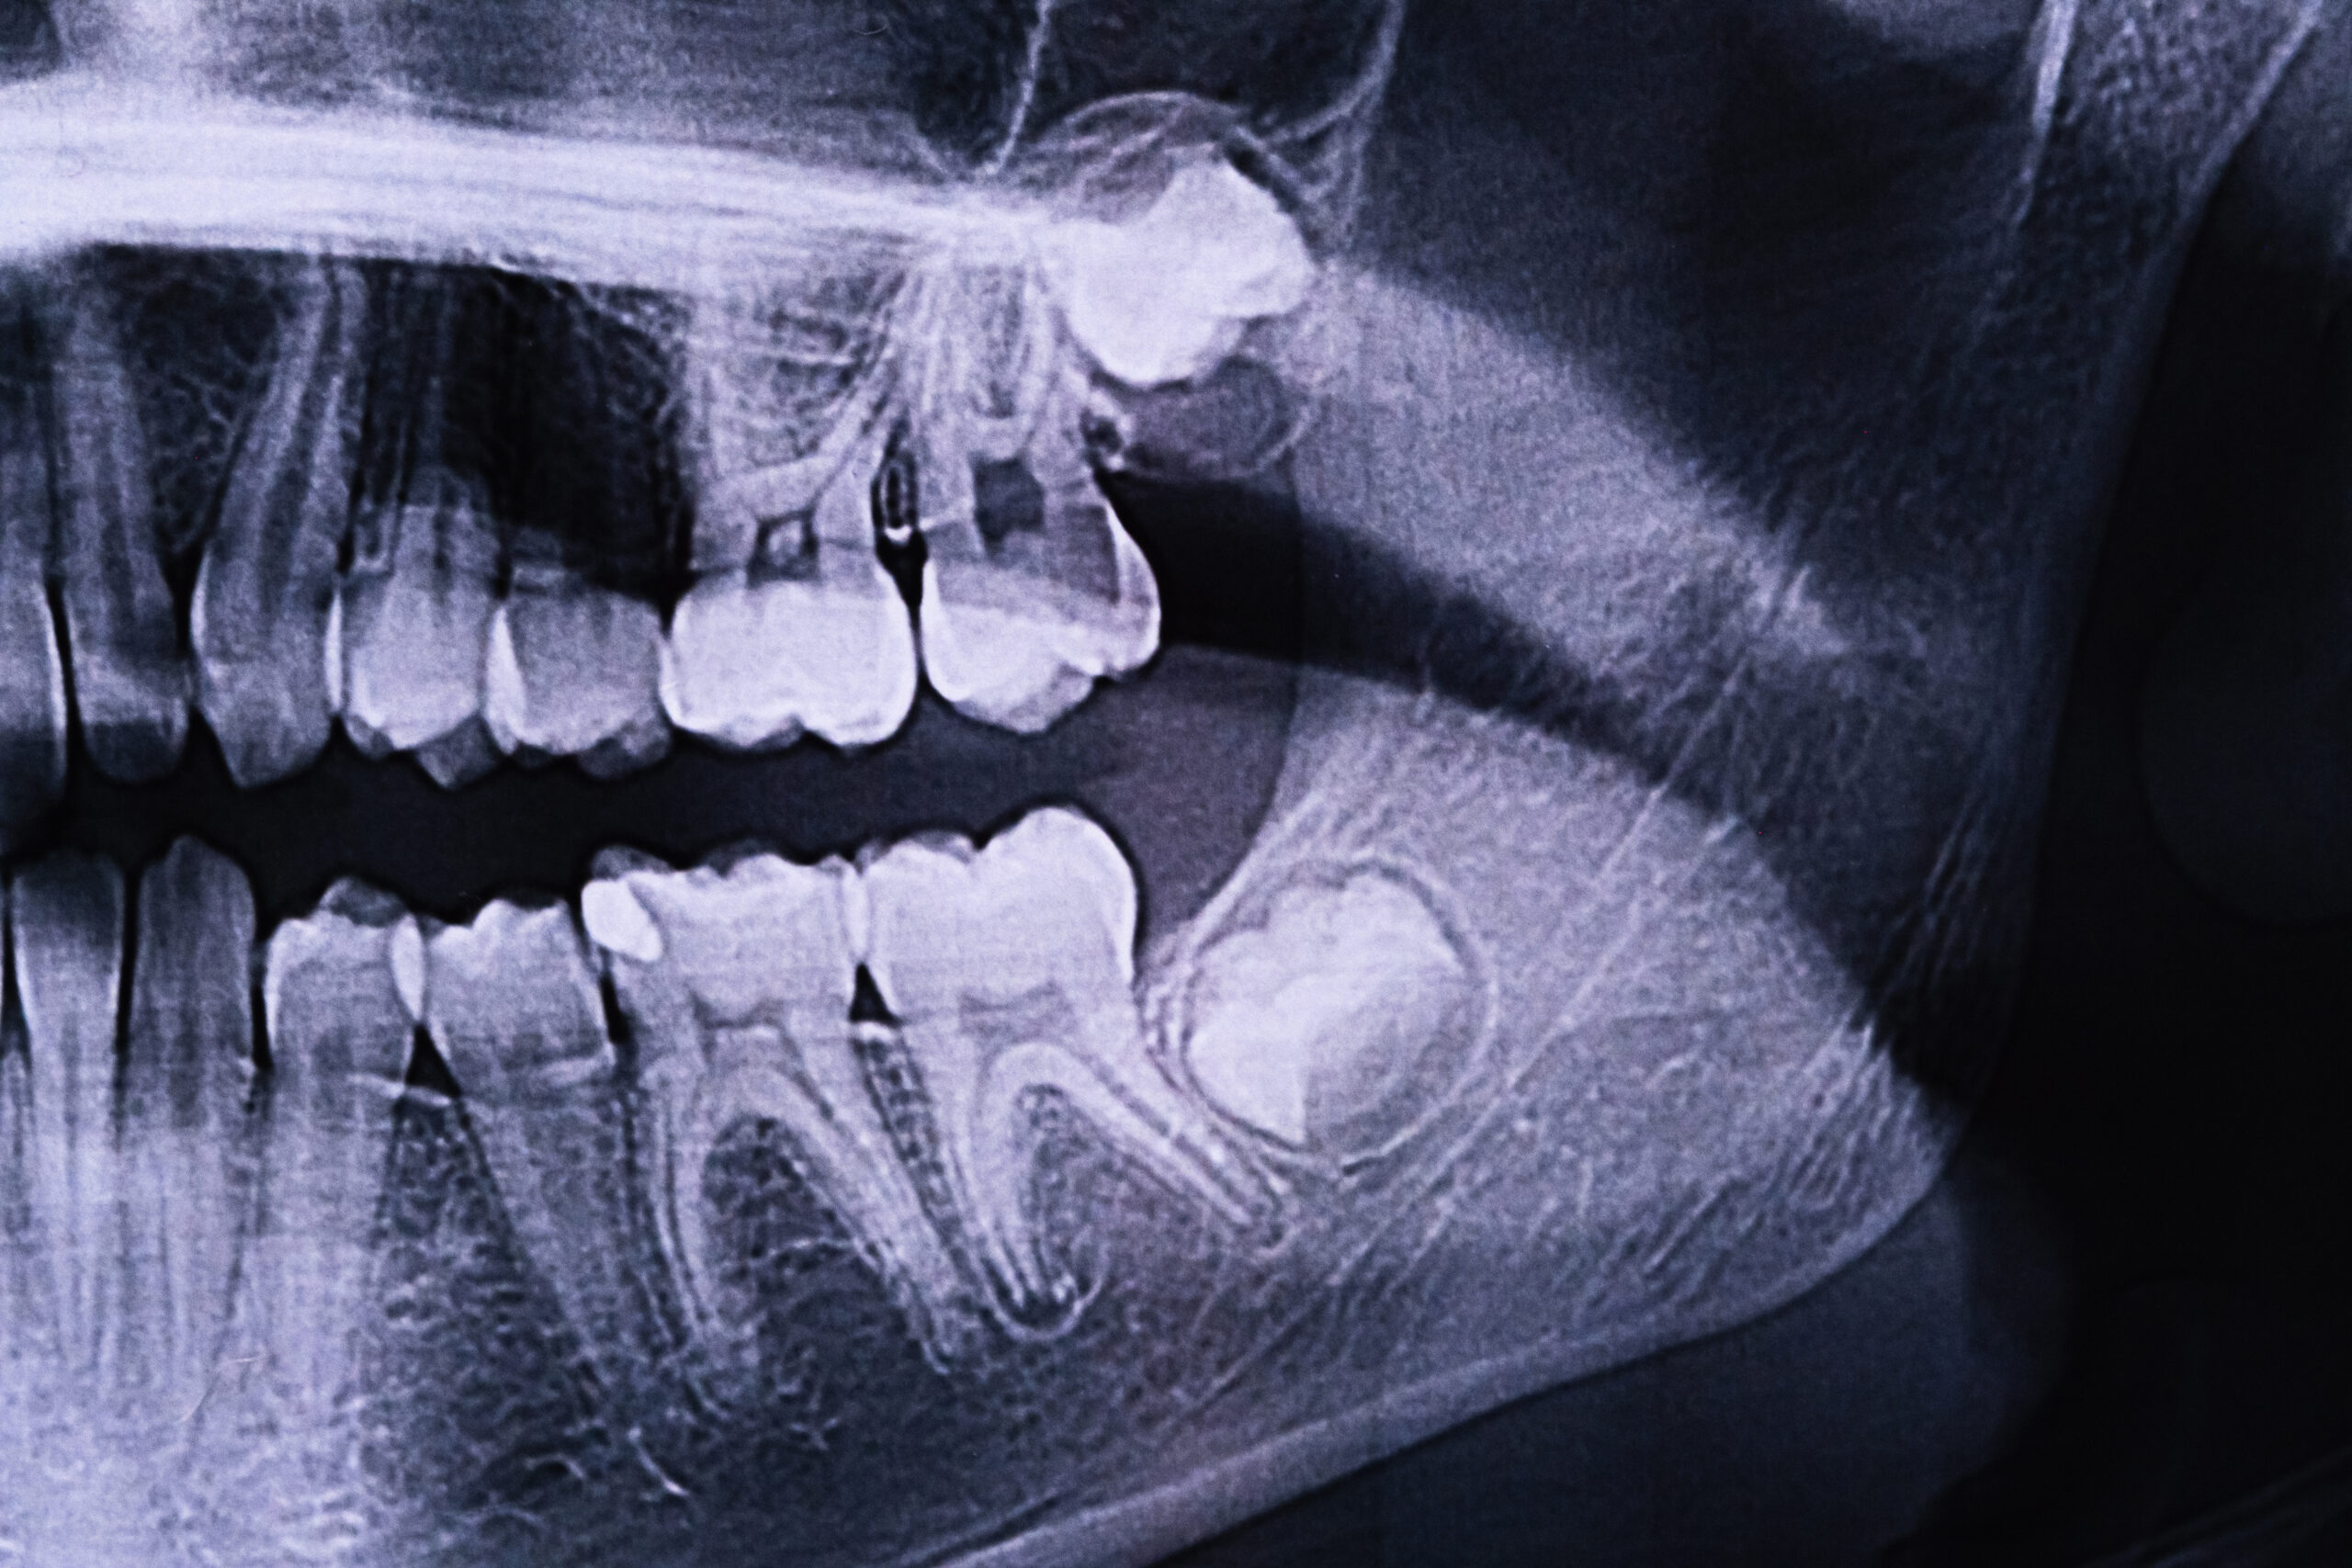

Panoramic X-ray & Exam

We start with a panoramic X-ray and exam to check position, root development, nerve proximity, and any active infection. We’ll explain your options and ideal timing — many wisdom teeth can be monitored safely; others are best removed proactively to avoid problems later.

Clear X-ray Review

We’ll show you where wisdom teeth sit and discuss the safest plan together.